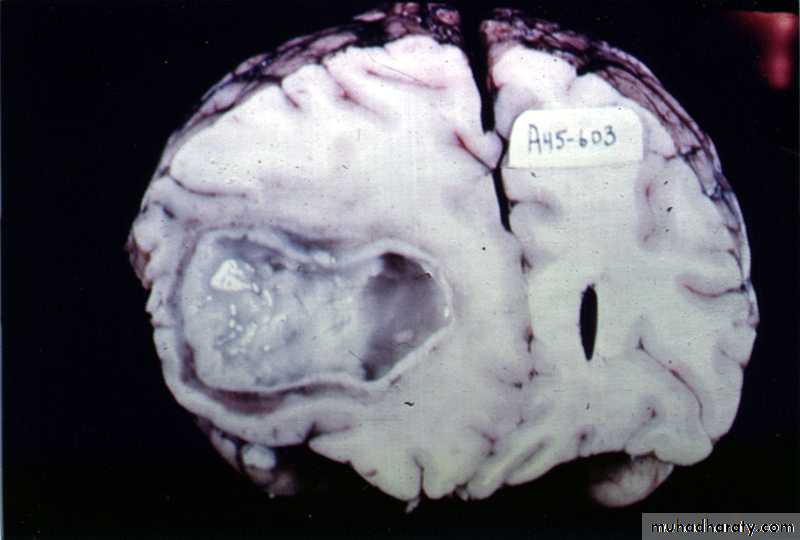

Pathology:

The formation of a collagen capsule in a developing abscess is the single most important responsible that limits the spread of infection to the rest of the brain.

Collagen capsule of brain abscess